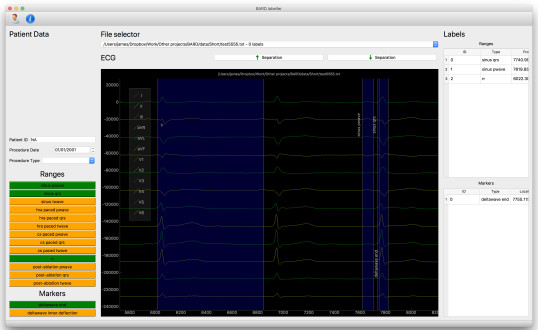

BARD ECG labelling system - LINK

An open source program to allow exporting of ECGs from the proprietary ‘BARD’ electrophysiology application. The program allows labelling of ECG waveforms to allow AI solutions to be trained on clinical ECG signals.